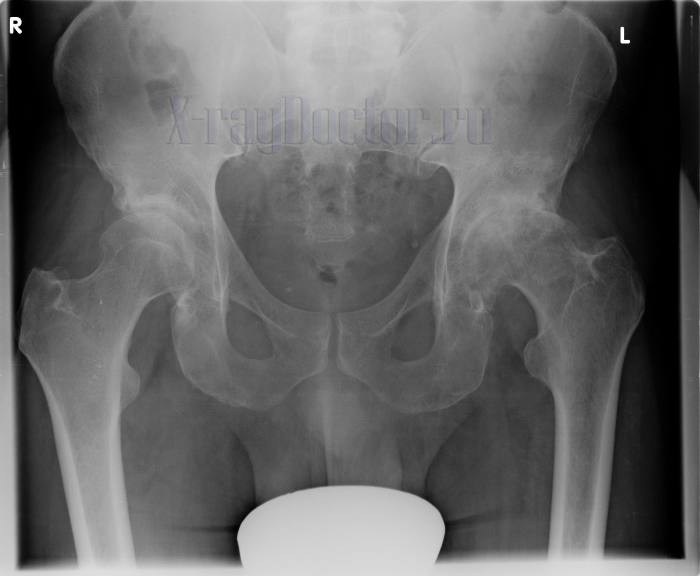

Рентгеновский снимок при коксартрозе

Протокол описания: На рентгенограмме тазобедренных суставов визуализируется нитевидное сужение суставной щели левого тазобедренного сустава (щель